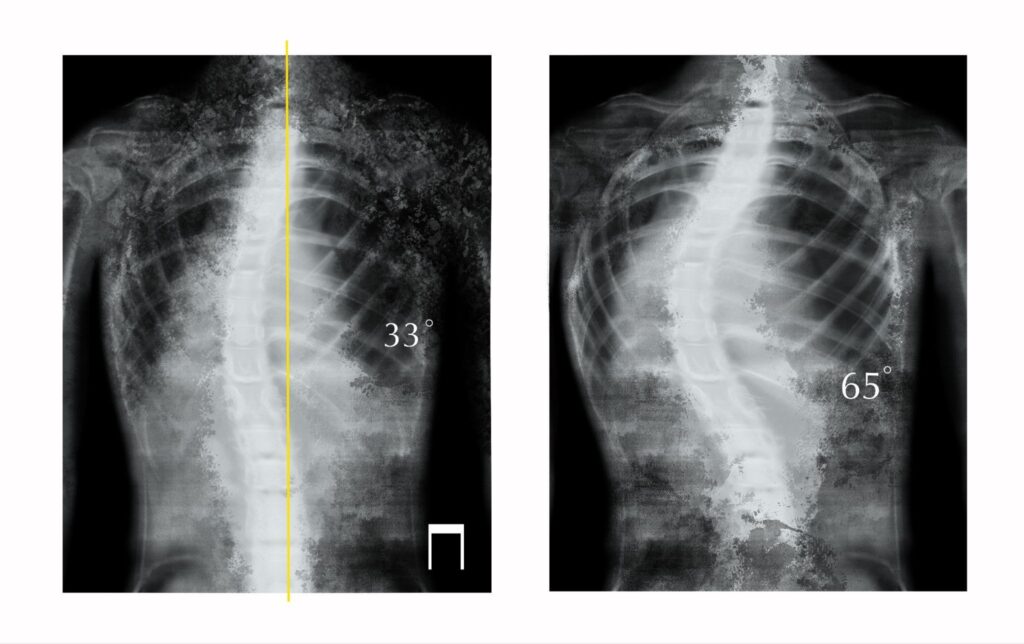

Scoliosis correction surgery is performed to address abnormal curvature of the spine that may lead to pain, imbalance, or neurological symptoms. The aim of surgery is to improve spinal alignment, stabilise the spine, and reduce the risk of further curve progression when non-surgical options are no longer sufficient.

Scoliosis refers to a sideways curvature of the spine that can develop during adolescence or adulthood. In adults, scoliosis is often associated with degenerative changes, spinal imbalance, or progression of a long-standing curve.

The decision to proceed with surgery depends on curve severity, spinal balance, symptom impact, and overall health.

The extent of surgery varies depending on the type and severity of scoliosis and may involve multiple levels of the spine.